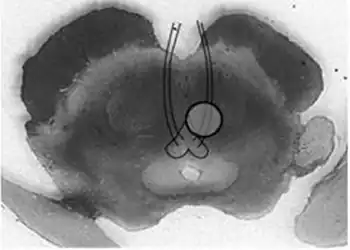

Benedikt syndrome. Localization of oculomotor fascicle injury and symptoms of Benedkit syndrome.

It is characterized by the presence of an oculomotor nerve (CN III) palsy and cerebellar ataxia including tremor and involuntary choreoathetotic movements. Neuroanatomical structures affected include the oculomotor nucleus, red nucleus, corticospinal tracts and superior cerebellar peduncle decussation. It has a similar cause, morphology, signs and symptoms to Weber's syndrome; the main difference between the two being that Weber's is more associated with hemiplegia (i.e. paralysis), and Benedikt's with hemiataxia (i.e. disturbed coordination of movements). It is also similar to Claude's syndrome, but is distinguishable in that Benedikt's has more predominant tremor and choreoathetotic movements while Claude's is more marked by the ataxia.